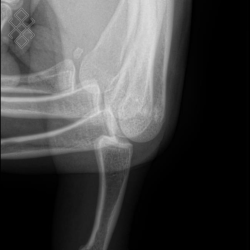

Radiographie du Doigt

Pour une radiographie du doigt, aucune préparation n'est requise. Il est recommandé d'enlever tous les bijoux avant de se présenter.

Vous serez installés en position assise avec la main posée sur un support.

La durée de l'examen est d'environ 5 minutes.

Après la fin de la radiographie du doigt, vous pourrez continuer vos activités de la journée sans problème. S'il y a eu une injection, le manipulateur en radiologie retirera le cathéter et il vous sera recommandé de boire beaucoup d'eau afin d'éliminer au mieux le produit de contraste.

Avant de passer une radiographie du doigt, il est primordial de signaler si vous êtes ou pensez être enceinte. En effet, vous devrez passer l'examen sous certaines conditions.